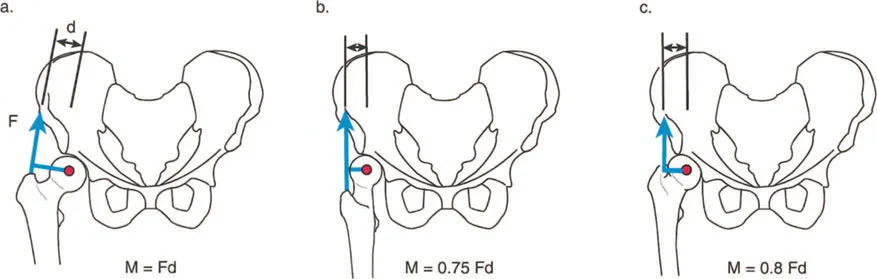

أمثلة أخرى رئيسية للتشوهات الديناميكية تشمل "الورم الفخذي المفرط" (Severe Femoral Anteversion) و "الورك الأفحج" (Coxa Vara). في كلتا هاتين الشذوذات المعمارية، يتم تقصير الطول الفيزيائي لذراع الرافعة لعضلات المبعدة (Abductor muscles) بشكل مرضي بسبب التشوه العظمي نفسه. قد تكون عضلة الألوية الوسطى (Gluteus Medius) صحية تمامًا، ومعصبة جيدًا، وقادرة على توليد قوة بيولوجية طبيعية، لكنها تعاني من خلل وظيفي سريري عميق لأن ميزتها الميكانيكية قد سُلبت بسبب الهندسة الهيكلية المتغيرة. هذه الفئة الفرعية المحددة من الأمراض تُعرف باسم "تشوه في طول ذراع الرافعة".

- الورك الأفحج (Coxa Vara): تشوه خلقي أو تطوري في عظم الفخذ يؤدي إلى تقصير ذراع الرافعة لعضلات الورك المبعدة، مما يضعف قدرتها على تثبيت الحوض.

- عرج ترندلنبورغ (Trendelenburg Lurch): في حالات ضعف عضلات الورك المبعدة (مثل الورك الأفحج)، يميل الحوض إلى السقوط على الجانب المقابل أثناء الوقوف على ساق واحدة، مما يؤدي إلى مشية متمايلة.